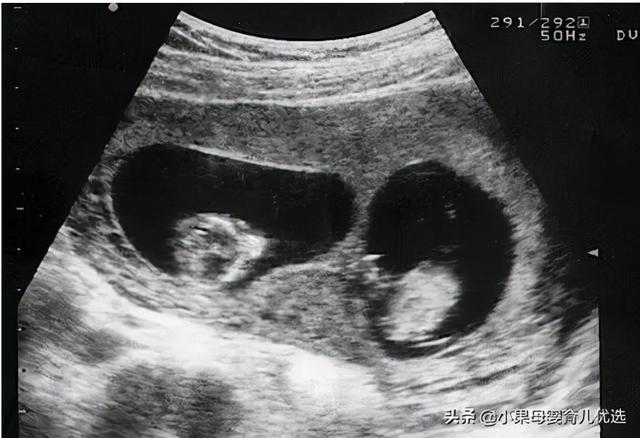

当时在产检的时候,医生通过b超发现她怀了两个宝宝。那一刻,她太高兴了,一出来就和丈夫分享了这个好消息。

当然,他们很兴奋,他们更好奇这是男宝还是女宝。当他们在一月份长大时,他们去看了那些男人和女人。令人惊讶的是这对双胞胎。